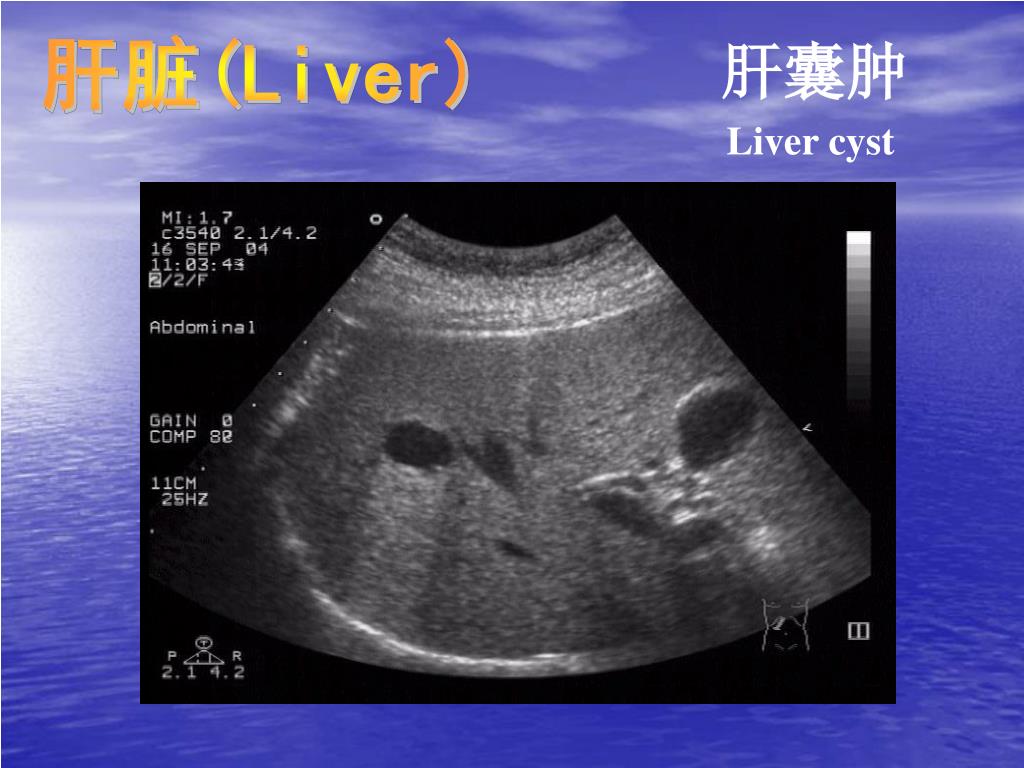

21. 肝脏(Liver) 肝囊肿 Liver cyst • 边清壁薄液性暗区伴后方回声增强 • anechoic lumen • clear wall • acoustic enhancement deep • to the lesion

22. 肝脏(Liver) 肝囊肿 Liver cyst

23. 肝脏(Liver) 肝囊肿 Liver cyst